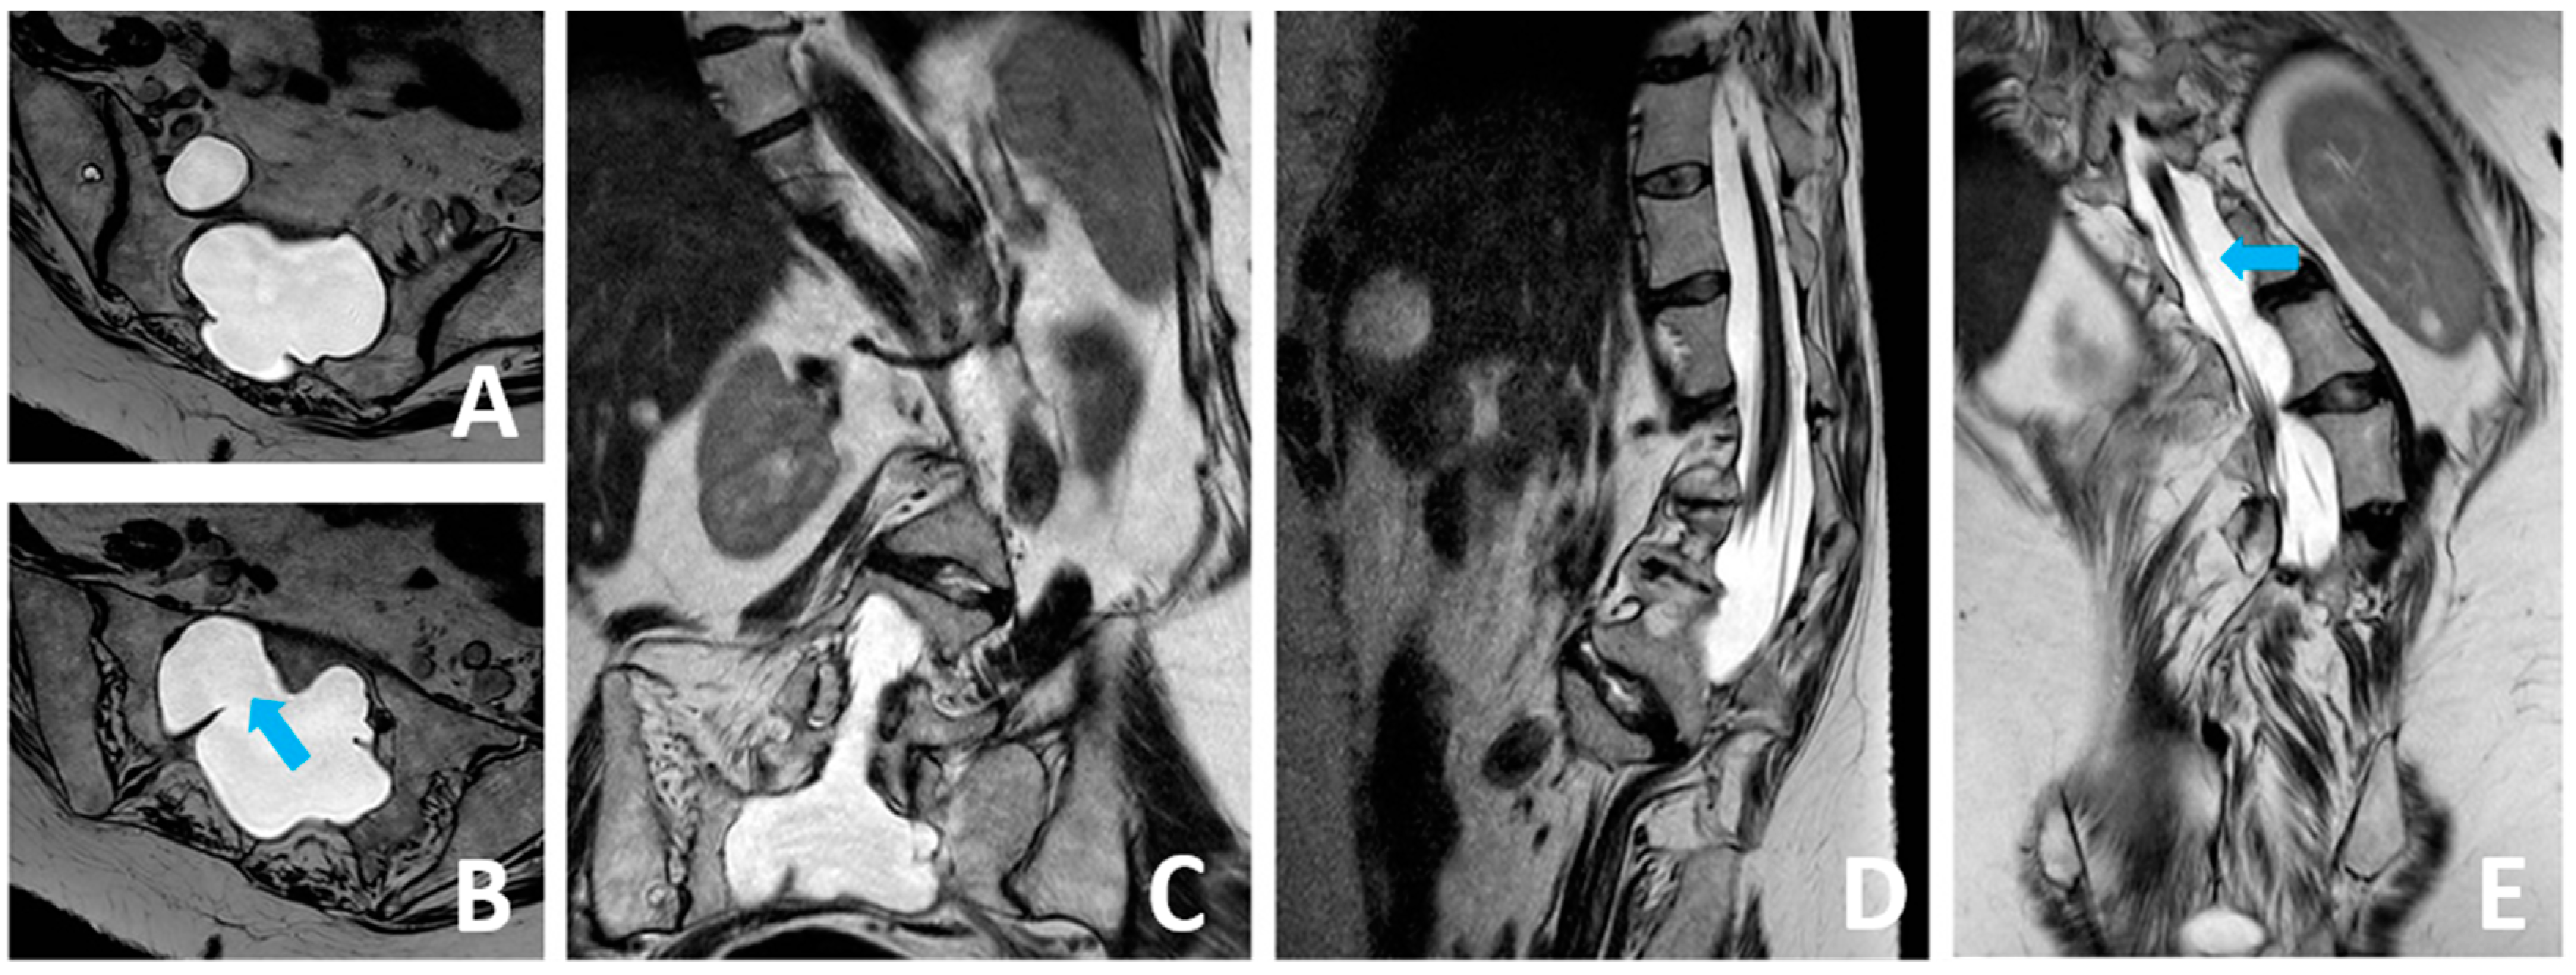

3.1. Case Presentation